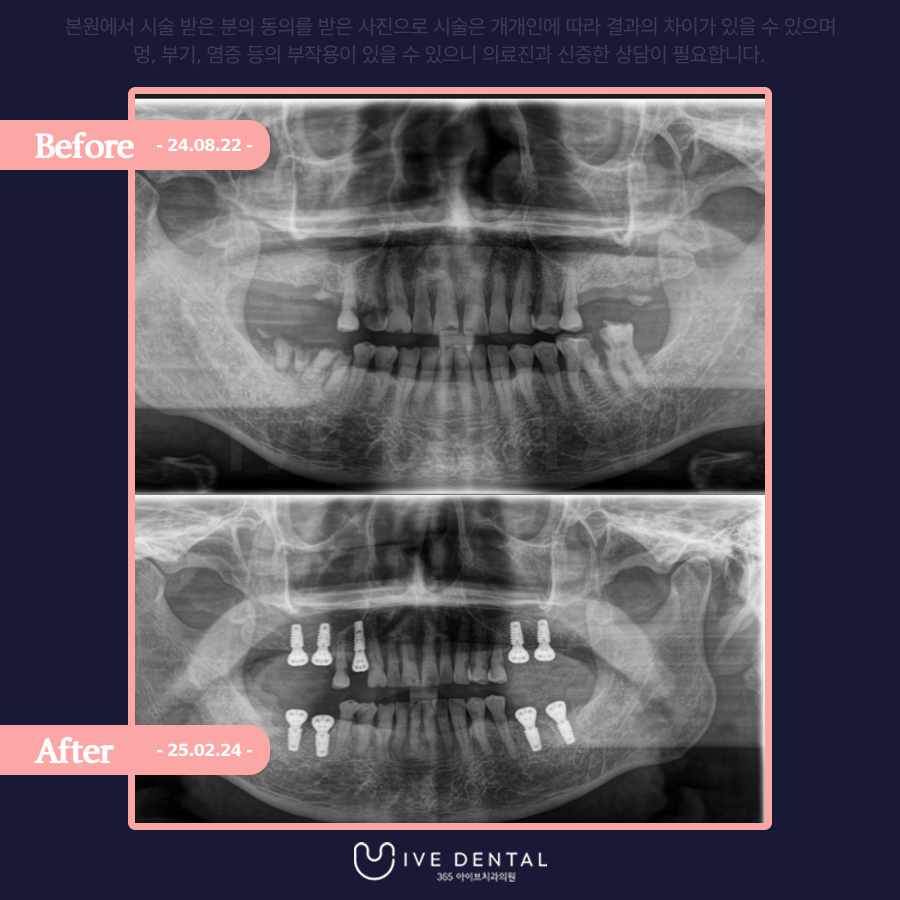

내원 시 찍은 X-ray 사진입니다.

잇몸 전체적으로 염증과 고름이 심하고 부식된 치아도 보입니다.

전체적으로 검진 후 살릴 수 있는 치아는 최대한 살리고 흔들림이 심하여 살릴 수 없는 치아는 뽑고 임플란트 시술을 하기로 하셨습니다.

당일에 수면치료로 임플란트를 식립한 후 사진입니다!

환자분께서도 당일에 통증을 해결하시고 수술까지 다 진행할 수 있어서 매우 만족해하셨고요.

임플란트 이외에 다른 충치 치료도 저희 치과에서 하시기로 하셨습니다.